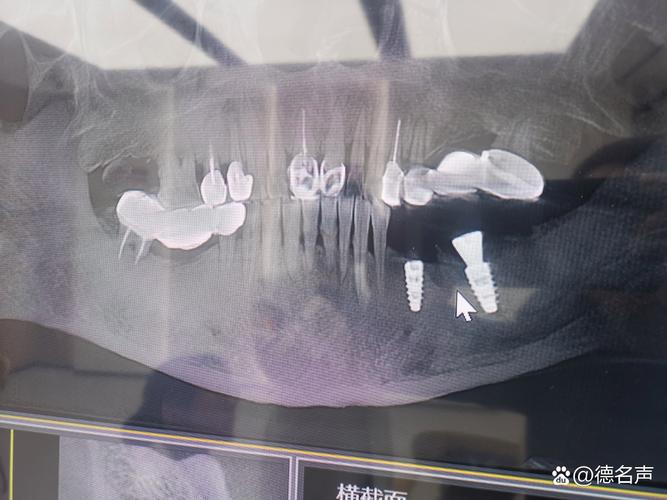

种牙手术的本质是将人工种植体植入牙槽骨内,使其与骨组织结合(骨整合),最终承担咀嚼功能,这一过程对牙槽骨的条件要求极高,而CBCT能通过三维成像,全面、精准地提供普通二维X光无法获取的关键信息:

- 骨量评估:准确测量牙槽骨的高度、厚度和长度,判断是否满足种植体植入的最低要求(通常种植体长度需8-10mm,直径3.5-5mm,骨厚度需至少1mm以上),若骨量不足,需提前进行植骨增量,否则可能导致种植体松动、脱落。

- 解剖结构定位:清晰显示下牙槽神经管、上颌窦、颏孔等重要解剖结构的位置与走行,下颌后牙区种植时,若种植体误入下牙槽神经管,可能造成下唇麻木等神经损伤;上颌后牙区种植时,若穿透上颌窦底,可能引发上颌窦炎,甚至导致种植体感染失败。

- 骨密度分析:骨密度直接影响种植体的初期稳定性,CBCT可通过灰度值评估骨密度(如D1-D4类骨),医生据此选择合适的种植体类型(如亲水性种植体适用于低密度骨),并调整植入扭矩,避免因骨密度过低导致种植体骨结合失败。

- 邻牙及软组织观察:了解邻牙牙根是否倾斜、有无根尖病变,以及牙龈厚度、附着龈宽度等,为种植体植入位置、角度设计提供依据,避免损伤邻牙或影响后期修复的美观与功能。